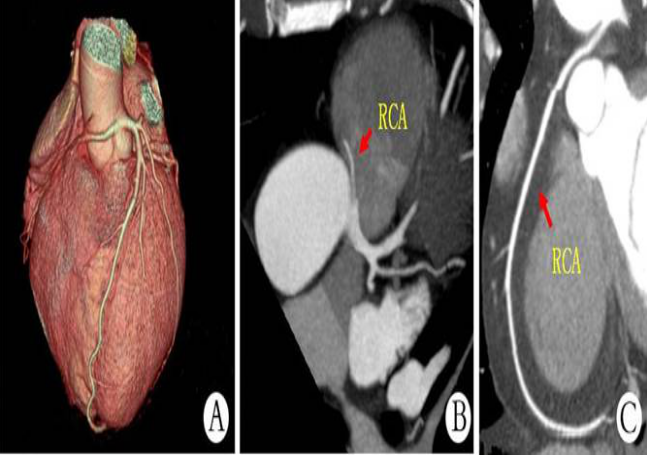

冠狀動(dòng)脈CTA檢查是一種經(jīng)靜脈注射造影劑后利用螺旋CT掃描再經(jīng)過(guò)計(jì)算機(jī)處理重建得出的心臟冠脈成像的一種影像學(xué)檢查方法。冠脈CTA可用于觀察冠狀動(dòng)脈有無(wú)斑塊形成,判斷血管狹窄情況,了解血管有無(wú)變異以及對(duì)與冠脈支架和搭橋術(shù)后進(jìn)行定期隨訪(fǎng),冠脈CTA優(yōu)勢(shì)在于;無(wú)創(chuàng),簡(jiǎn)便易行,無(wú)需住院,價(jià)格相對(duì)低廉,多角度觀察血管剖面。